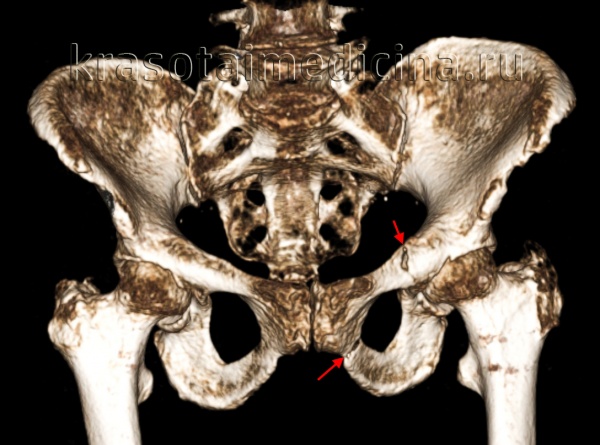

(Справа) КТ, аксиальный срез: у этот же пациента определяется диффузное расширение левого КПС, указывающее на полный разрыв передних и задних связок левого крестцово-подвздошного сочленения. Правое крестцово-подвздошное сочленение расширено только спереди. (Слева) КТ, 3D реконструкция: у женщины 75 лет определяются переломы по типу ЛК I. Отмечаются косые переломы ветви лобковой кости слева и вколоченный перелом 2 зоны крестца слева.

(Справа) КТ, 3D реконструкция: у мужчины 50 лет определяется травма по типу ПЗК II. Лобковый симфиз расширен >2,5 см. Левое крестцово-подвздошное сочленение расширено спереди, но сзади нормальное. Задние крестцово-подвздошные/ сочленения/связки также должны быть оценены на других проекциях, поскольку при разрыве формируется нестабильная травма по типу ПЗК III.